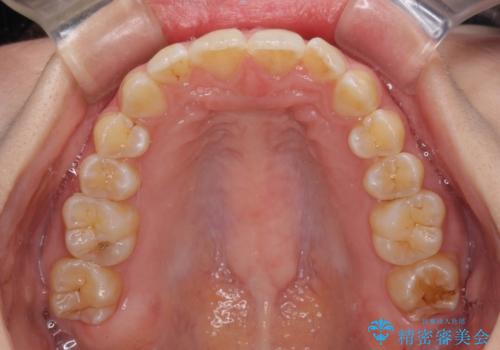

前歯のデコボコを解消 インビザラインによる矯正治療

- 上下前歯のデコボコと深い咬み合わせを気にして来院された患者様です。

インビザラインによる上下歯列の拡大と、IPR(歯と歯の間を削る)にるスペースの獲得により、前歯のデコボコを改善することとしました。

上の前歯をもう少し整えたかったのですが、患者様の治療を早く終了させたいという希望により、細かい叢生を残しての終了となりました。